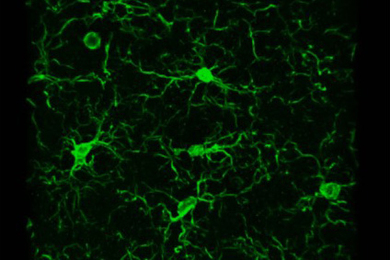

Study indicates ailing neurons may instigate an inflammatory response from the brain’s microglia immune cells.

Research reveals cells that span brain hemispheres to coordinate activity in visual processing centers, shows Alzheimer’s degrades their structure and function.

A breakdown of lipid metabolism in these brain cells promotes inflammation and interferes with neuron activity, a new study finds.